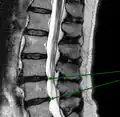

L'imagerie par résonance magnétique peut montrer la hernie, le canal vertébral, les nerfs, les tissus environnants. Les tissus mous sont les mieux analysés par cet examen qui est le plus performant pour le diagnostic de hernie discale. Les images pondérées en T2 montrent clairement la hernie.

IRM lombosacrée sagittale montrant une hernie discale de niveau L4-L5.

IRM lombaire sagittale montrant une hernie discale de niveau L4-L5.

IRM lombaire sagittale montrant une hernie discale de niveau L4-L5.- IRM lombaire sagittale montrant des protrusions discales.